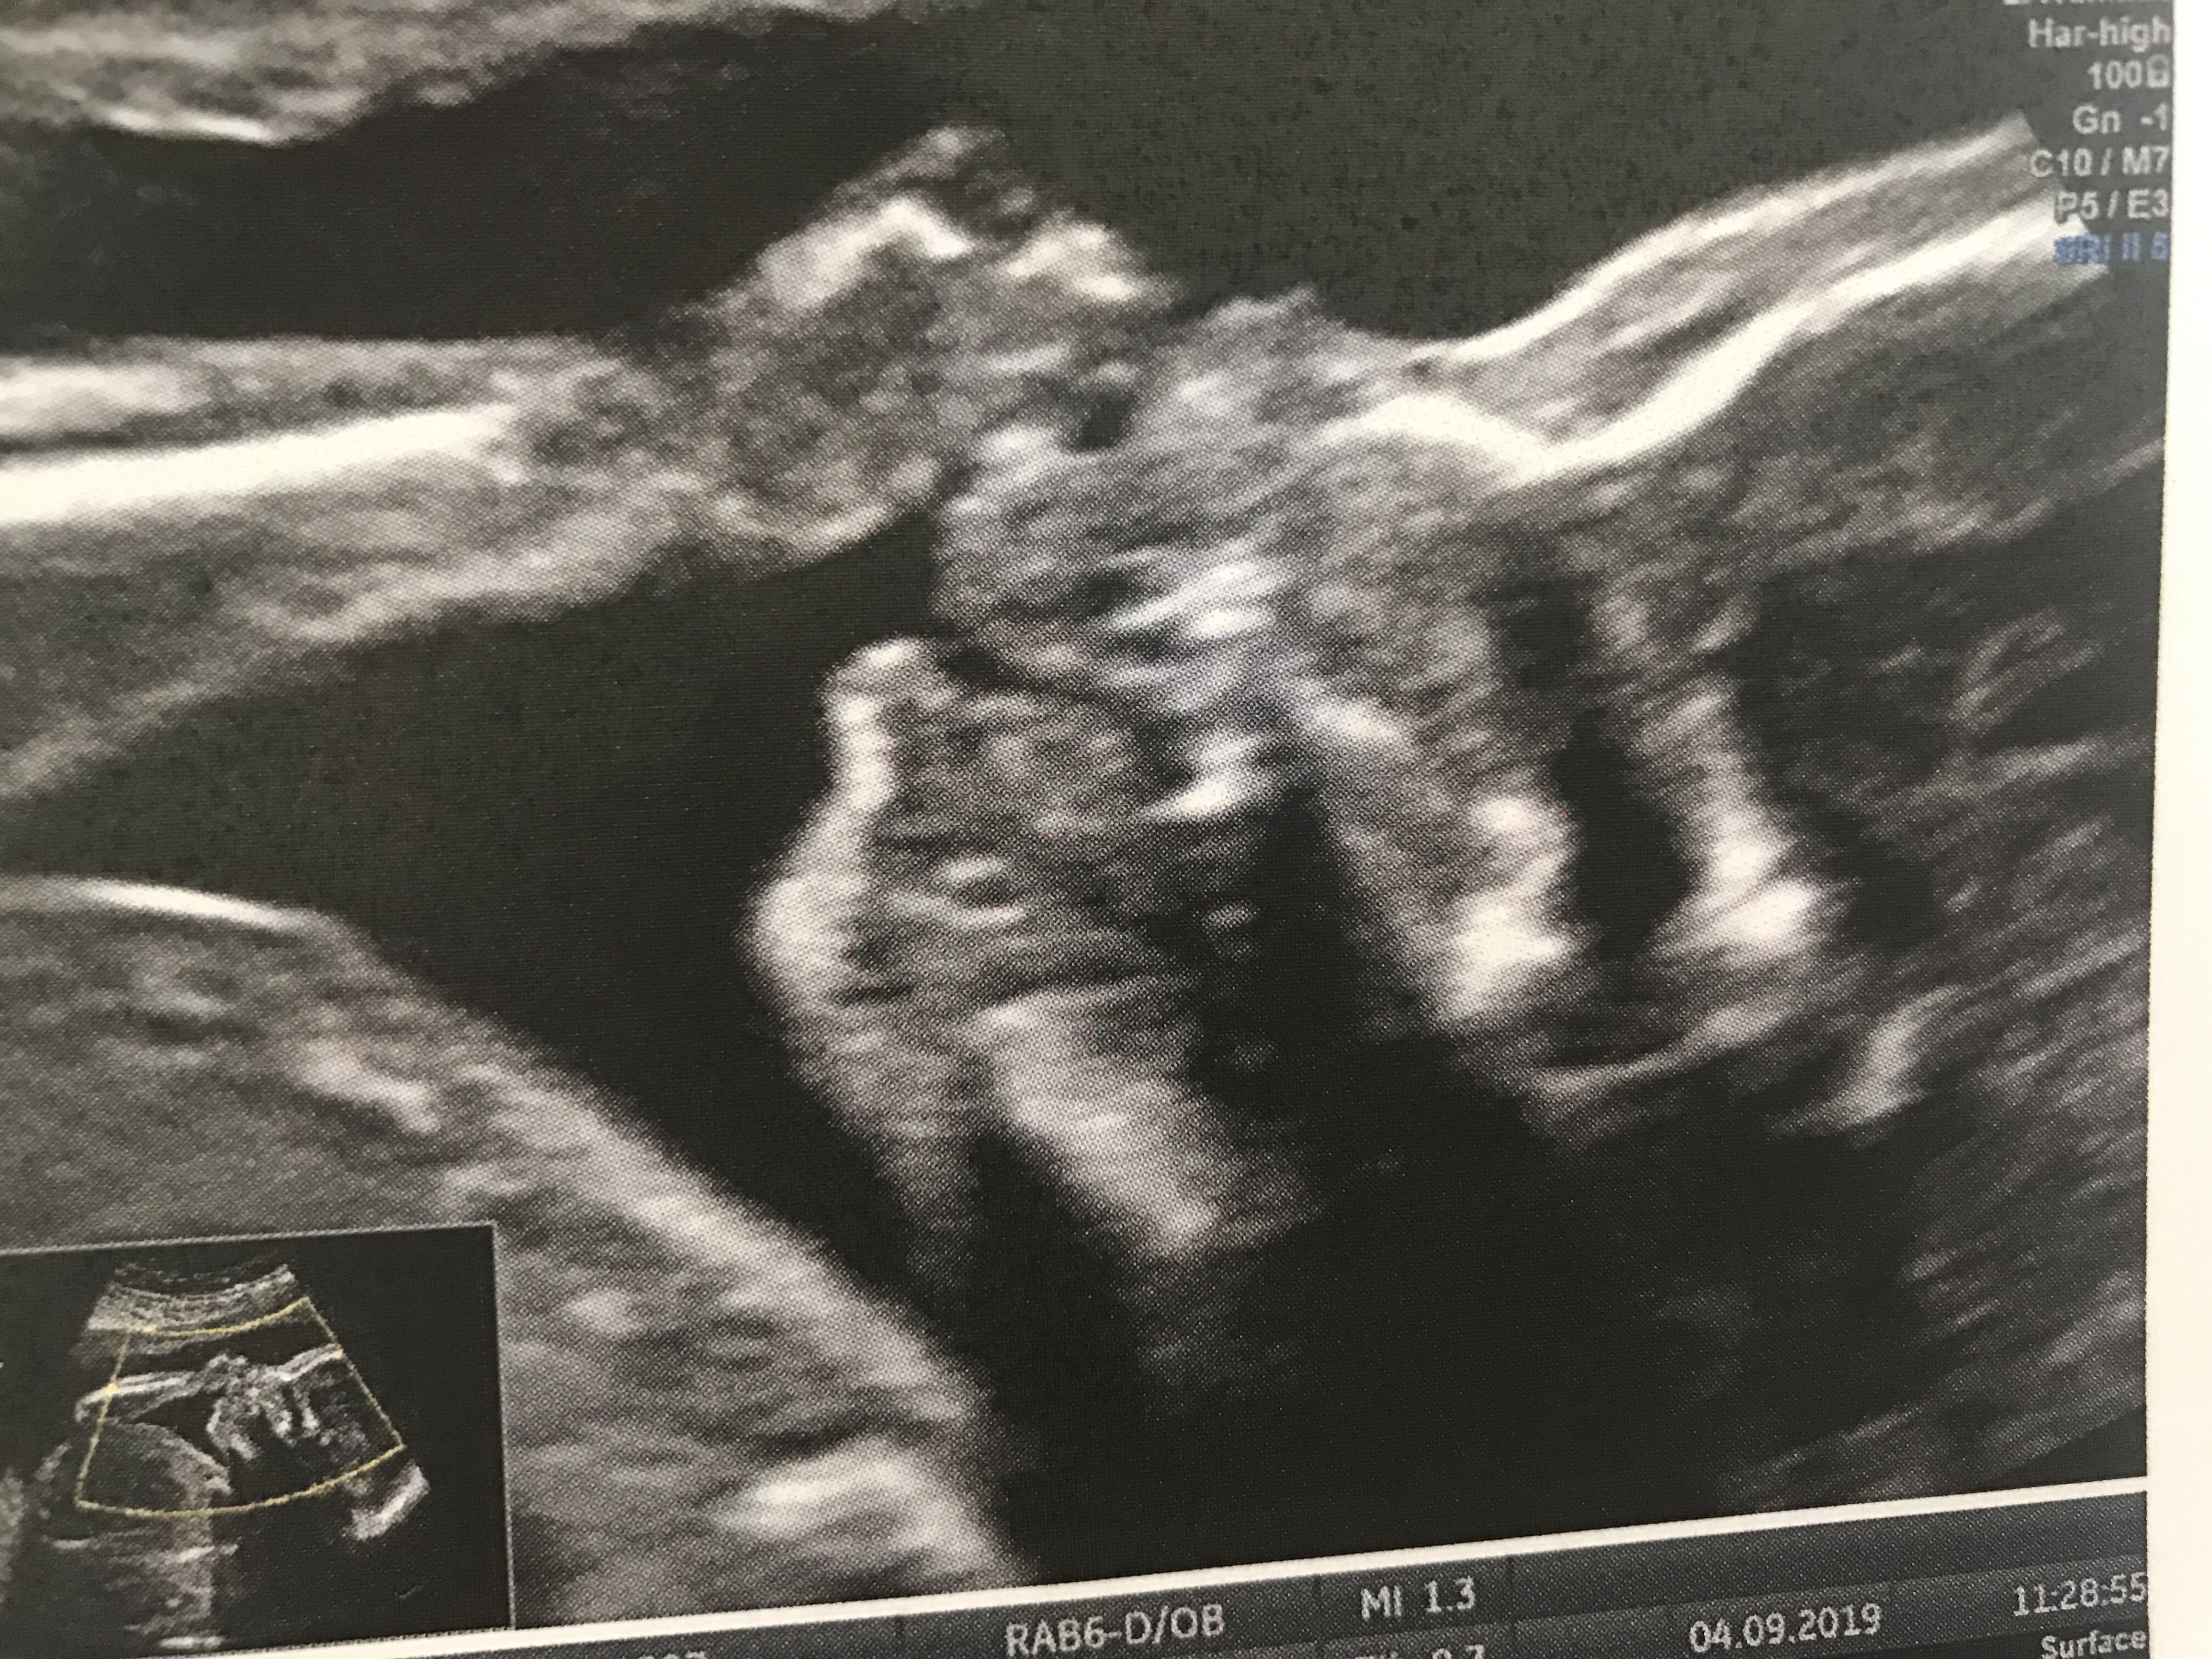

Wróciłam z prenatalnych połówkowych. 323 g, ciąża młodsza o tydzień, parametry odpowiadają 20 tygodniowi,nie 21. Mała ma niedomykalnosc zastawki trójdzielnej. Piszę m ała, ale lekarz znów mówi że nie pokazała i tak mu się wydaje. 19 jadę na echo serca do szpitala o 3 stopniu referencyjnosci.

Co do wady serca - tu trochę bardziej skomplikowane. Układ krwionośny rozwija się i na tym etapie nie mówił o wadze jak u dorosłego, ale jak u wadzie płodu - może się wchlonac, zastawka będzie prawidłowa, może być wada. Najwyżej czeka mnie poród w CZDz w Warszawie. A na razie badanie echa u ginekologa - kardiologa/neonatologa.